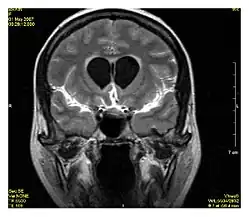

La séquence atténuation fluidique par inversion-récupération (Fluid-attenuated inversion recovery (FLAIR)) est une séquence IRM en inversion-récupération qui annule le signal des fluides. Cette séquence est généralement utilisée pour l'IRM cérébrale pour atténuer le signal du liquide cérébrospinal (LCS), ce qui permet de mieux observer certaines pathologies, notamment celles présentes à l'interface parenchyme-LCS[1],[2]. La séquence fut développée dans les années 1990 par l'équipe de recherche de Hammersmith (constituée de Graeme Bydder, Joseph Hajnal, et Ian Young)[3].

La séquence FLAIR est particulièrement utile dans l'évaluation et l'étude des troubles du système nerveux central (SNC), notamment [4]: